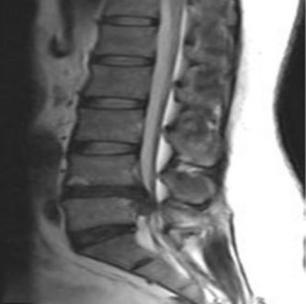

• 不同入路脊柱内镜手术治疗L4/5节段脱垂型腰椎间盘突出症的疗效比较

摘要:目的 观察经椎间孔入路内镜下腰椎间盘切除术(TELD)和经椎板间入路内镜下腰椎间盘摘除术(IELD)治疗L4/5节段脱垂型腰椎间盘突出症(LDH)的临床疗效。方法 回顾性分析2020年11月-2022年11月该院采用脊柱内镜手术治疗的75例L4/5节段脱垂型LDH患者的临床资料。根据手术入路的不同,将患者分为TELD组(53例)和IELD组(22例)。比较两组患者的手术情况和术后疗效。结果 与TELD组比较,IELD组的手术时间明显缩短,术中透视次数明显减少,差异均有统计学意义(P < 0.05);两组患者住院时间和并发症发生率比较,差异均无统计学意义(P > 0.05)。所有患者术后均获得12~19个月的随访。两组患者末次随访时的视觉模拟评分法(VAS)评分和Oswestry功能障碍指数(ODI)明显低于术前,且IELD组明显低于TELD组,差异均有统计学意义(P < 0.05)。按照突出物和神经根的不同位置进一步分析,两组肩上型患者(TELD组10例,IELD组6例)末次随访时的VAS评分和ODI明显低于术前,且IELD组末次随访时的VAS评分明显低于TELD组,差异均有统计学意义(P < 0.05);两组腋下型患者(TELD组8例,IELD组16例)末次随访时的VAS评分和ODI明显低于术前,且IELD组明显低于TELD组,差异均有统计学意义(P < 0.05);35例肩前型患者经TELD术后,末次随访时的VAS评分和ODI明显低于术前,差异有统计学意义(P < 0.05)。按照突出物的不同Lee分区进一步分析,两组Lee Ⅲ区患者(TELD组44例,IELD组10例)末次随访时的VAS评分和ODI明显低于术前,且IELD组的ODI明显低于TELD组,差异均有统计学意义(P < 0.05);两组Lee Ⅳ区患者(TELD组9例,IELD组12例)末次随访时的VAS评分和ODI明显低于术前,且IELD组明显低于TELD组,差异均有统计学意义(P < 0.05)。结论 采用TELD和IELD治疗L4/5节段脱垂型LDH,均可获得较满意的减压效果,但IELD的手术时间相对较短,X线透视次数较少,且对肩上型、腋下型、Lee Ⅲ区和Lee Ⅳ区的减压效果更有优势。